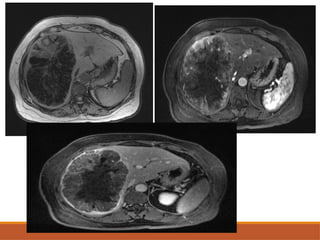

• #31 Axial cect images of hcc in segment 4a in showing enhancement odf elsion in arterial phase and washout of tumour in portal venous phase and delayed phases So early washout of the contrast suggestive of hcc

• #33 Axial t2 weighted image showing hetrogebous intensity lesion in right lobe of liber with heterogenous enhancenment in arterial phase nafd washout of contrast in portal venous phase